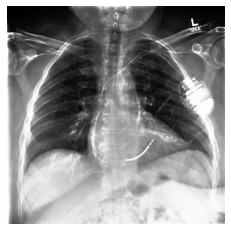

Automated diagnosis prediction from medical images is a valuable resource to support clinical decision-making. However, such systems usually need to be trained on large amounts of annotated data, which often is scarce in the medical domain. Zero-shot methods address this challenge by allowing a flexible adaption to new settings with different clinical findings without relying on labeled data. Further, to integrate automated diagnosis in the clinical workflow, methods should be transparent and explainable, increasing medical professionals' trust and facilitating correctness verification. In this work, we introduce Xplainer, a novel framework for explainable zero-shot diagnosis in the clinical setting. Xplainer adapts the classification-by-description approach of contrastive vision-language models to the multi-label medical diagnosis task. Specifically, instead of directly predicting a diagnosis, we prompt the model to classify the existence of descriptive observations, which a radiologist would look for on an X-Ray scan, and use the descriptor probabilities to estimate the likelihood of a diagnosis. Our model is explainable by design, as the final diagnosis prediction is directly based on the prediction of the underlying descriptors. We evaluate Xplainer on two chest X-ray datasets, CheXpert and ChestX-ray14, and demonstrate its effectiveness in improving the performance and explainability of zero-shot diagnosis. Our results suggest that Xplainer provides a more detailed understanding of the decision-making process and can be a valuable tool for clinical diagnosis.